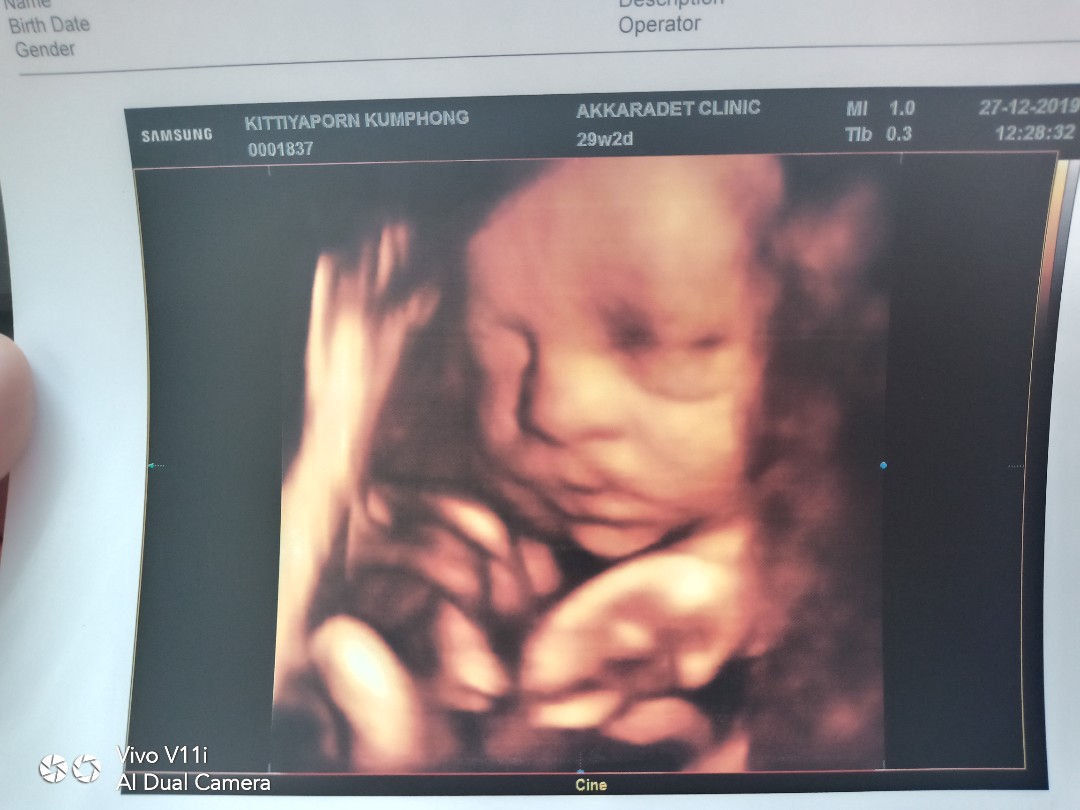

กว่าจะได้แบบนี้ ลุ้นตั้งนาน

ซาว2รอบกว่าจะยอมให้เห็นหน้า

ซาวด์ตอน27weekจ้า ตอนนี้33+2weekแล้ว